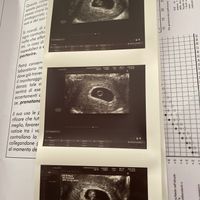

Apro in puntissima di piedi questo post..dopo un aborto di 4 anni fa e una diagnosi di infertilità maschile,mi ritrovo incinta di 4 settimane con una totale assenza di sintomi e tanta paura❤️...